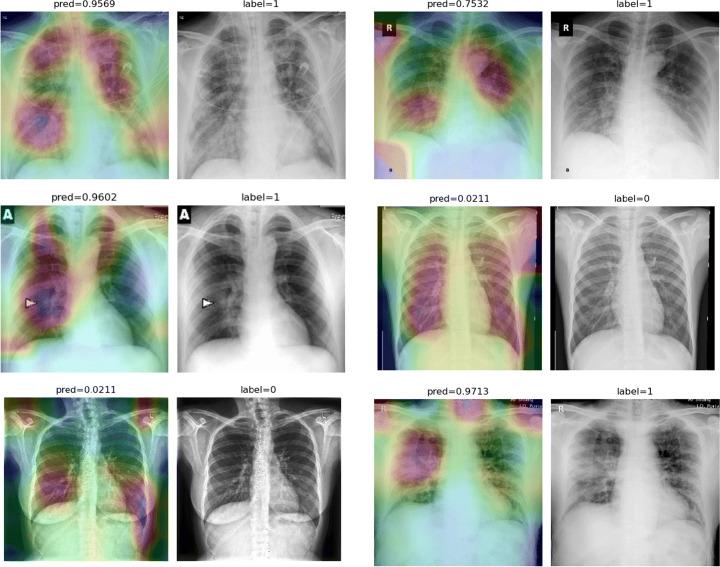

One of the primary clinical observations for screening the novel coronavirus is capturing a chest x-ray image. In most patients, a chest x-ray contains abnormalities, such as consolidation, resulting from COVID-19 viral pneumonia. In this study, research is conducted on efficiently detecting imaging features of this type of pneumonia using deep convolutional neural networks in a large dataset. It is demonstrated that simple models, alongside the majority of pretrained networks in the literature, focus on irrelevant features for decision-making. In this paper, numerous chest x-ray images from several sources are collected, and one of the largest publicly accessible datasets is prepared. Finally, using the transfer learning paradigm, the well-known CheXNet model is utilized to develop COVID-CXNet. This powerful model is capable of detecting the novel coronavirus pneumonia based on relevant and meaningful features with precise localization. COVID-CXNet is a step towards a fully automated and robust COVID-19 detection system.

筛查新型冠状病毒的主要临床观察方法之一是拍摄胸部X光图像。在大多数患者中,胸部X光显示出由COVID-19病毒性肺炎引起的异常,如实变。在本研究中,我们利用深度卷积神经网络在一个大型数据集中对这种类型肺炎的成像特征进行高效检测。结果表明,简单模型以及文献中的大多数预训练网络都关注于与决策无关的特征。本文收集了来自多个来源的大量胸部X光图像,并准备了一个最大的公开可用数据集。最后,使用迁移学习范式,利用著名的CheXNet模型开发了COVID-CXNet。这个强大的模型能够基于相关且有意义的特征精确地定位检测新型冠状病毒肺炎。COVID-CXNet朝着全自动且强大的COVID-19检测系统迈出了一步。